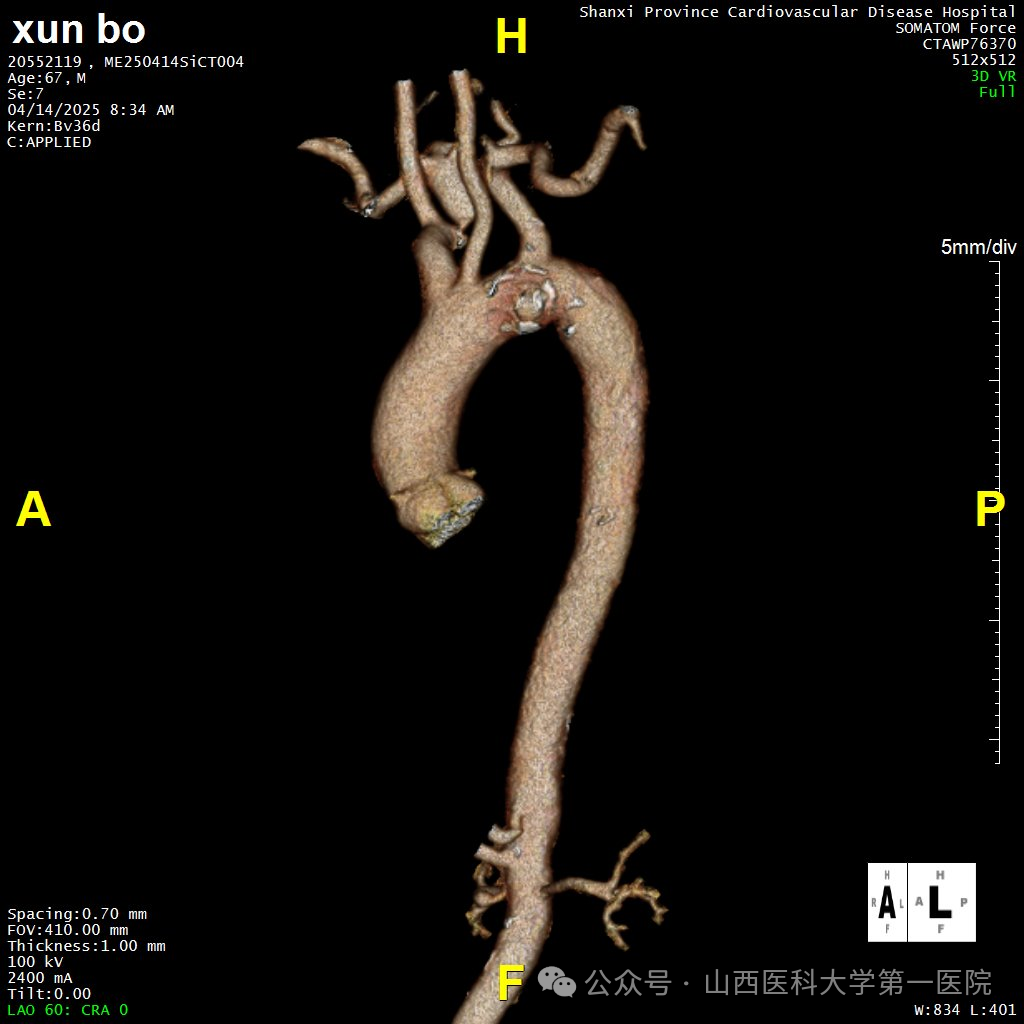

术前CTA

67岁男性患者既往有高血压病史,因反复胸背部不适入院。CTA检查提示其降主动脉左锁骨下动脉开口水平处存在一处穿透性溃疡,病灶大小约为1.9×1.0cm,穿透性溃疡位置累及左锁骨下动脉,主动脉穿透性溃疡可能发展成主动脉夹层、主动脉破裂,危及生命。